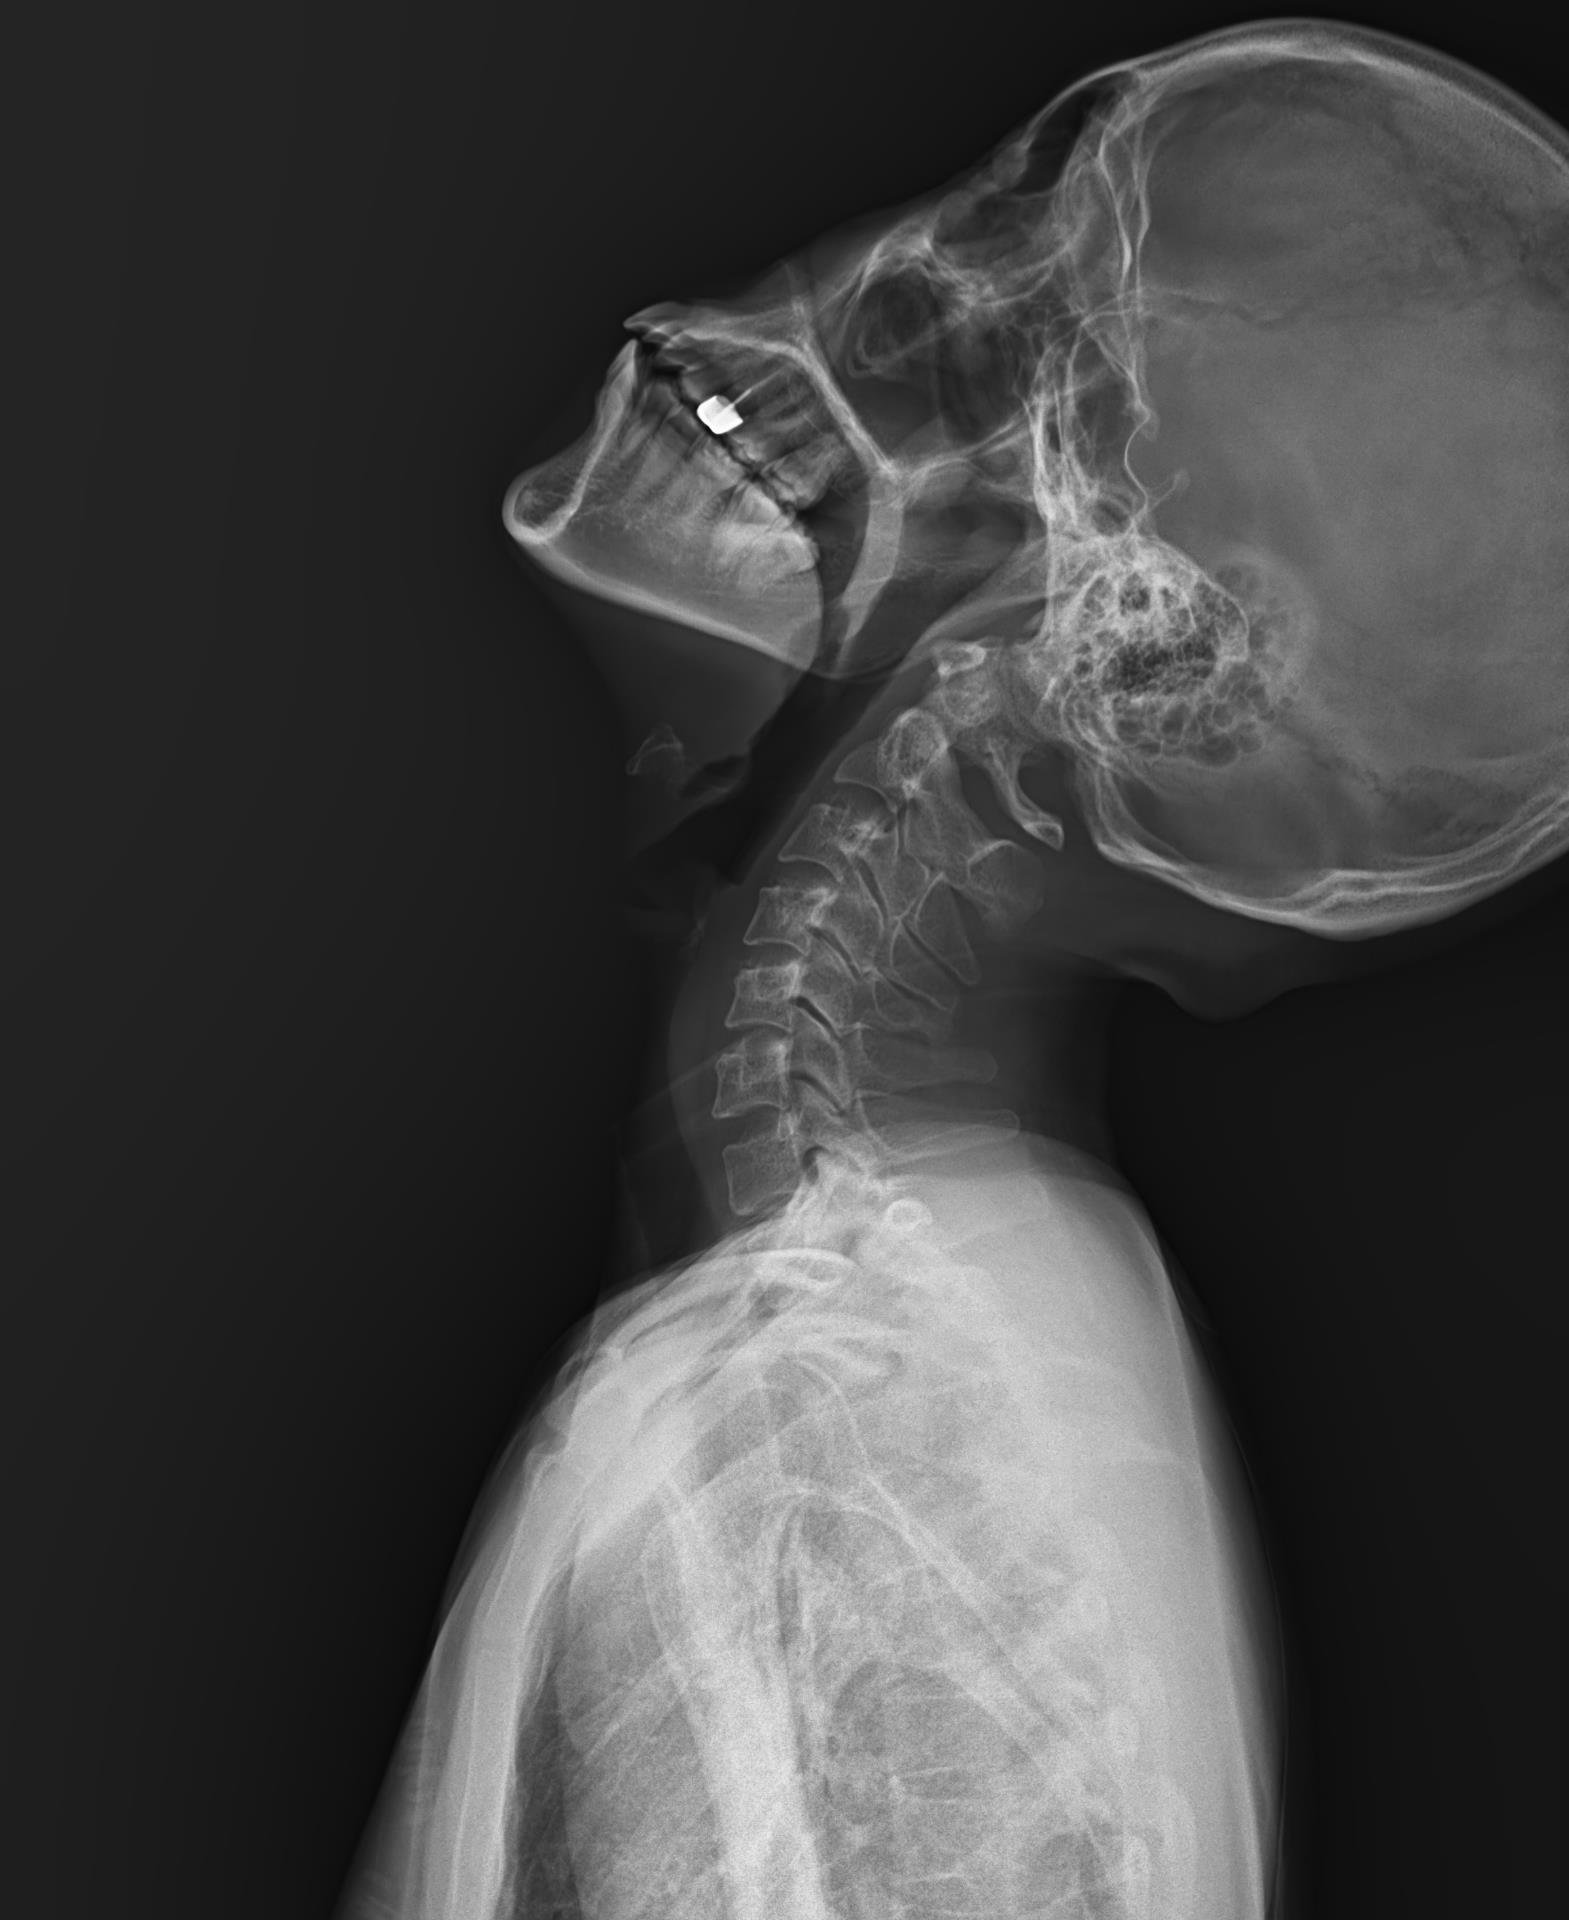

Ảnh chụp X-Quang cột sống (ảnh trên: một phần, ảnh dưới: toàn phần)